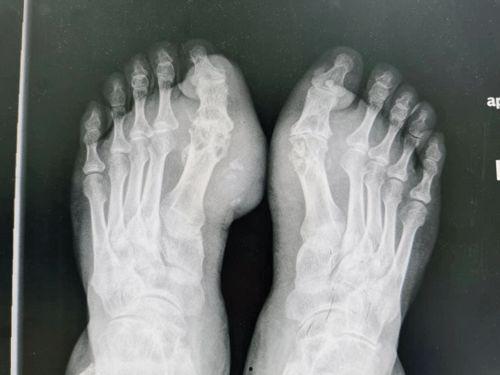

那么,痛风到底会在男人的哪些部位“安家”呢?这就得借助“男人痛风位置图”来一探究竟了。

1. 脚趾关节:痛风最典型的症状就是脚趾关节疼痛,尤其是大脚趾关节。这是因为脚趾关节承受的压力较大,尿酸在这里更容易沉积。

2. 踝关节:除了脚趾关节,踝关节也是痛风的高发区域。当尿酸在踝关节沉积时,会导致关节肿胀、红肿和疼痛。